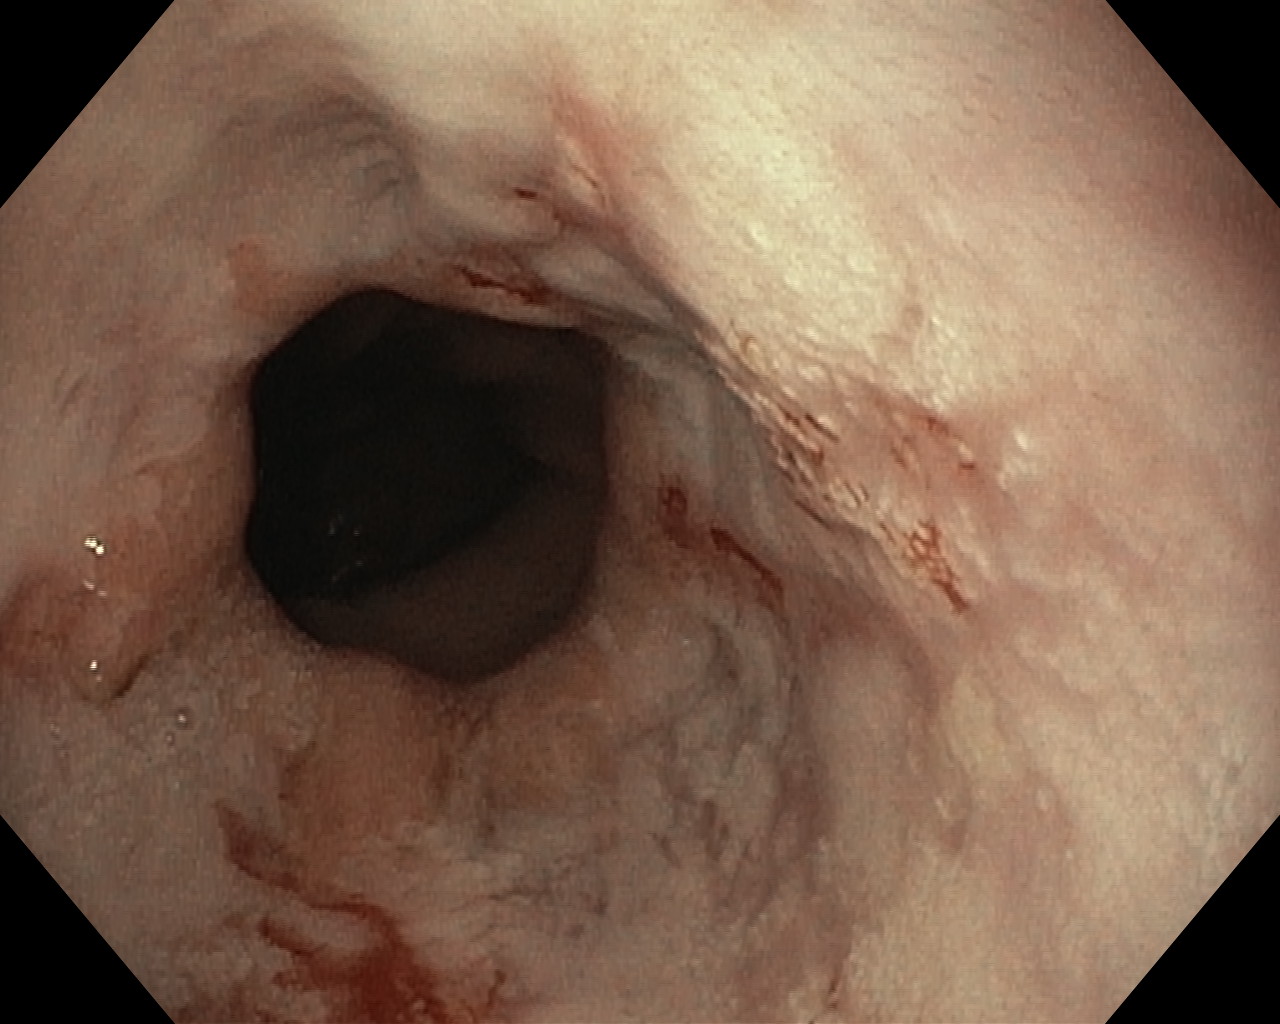

Choroba refluksowa